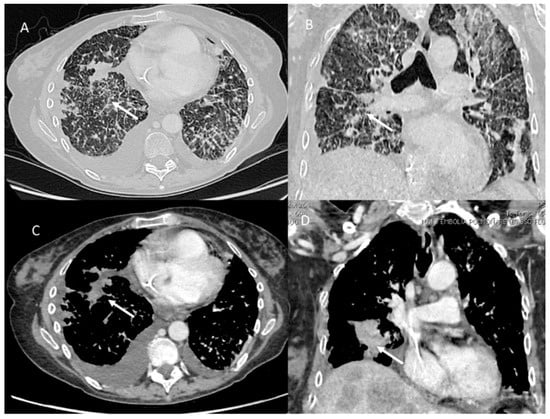

2. Immune Checkpoint Inhibitor-Related Pneumonitis

| Type of Pneumonia | Lung Involvement | CT-Patter |

|---|---|---|

| COVID-19 Pneumonia | Diffuse (related to the phase of disease) | ground-glass opacity, crazy-paving pattern, consolidative opacities, interlobular septal thickening (according to the phase of disease) |

| RRR-Related Vaccine | Target Area | Consolidative opacities |

| Pulmonary lymphangitis carcinomatosa | Diffuse (related to the phase of disease) | Irregularly interlobular septal thickening, smooth (early stage), or nodular thickening (late development), ground-glass opacity, pleural effusions. |

| ICI-Related Pneumonitis | Diffuse (related to the phase of disease) | ground-glass and reticular opacities, consolidative opacities, interlobular septal thickening, “crazy-paving” pattern |